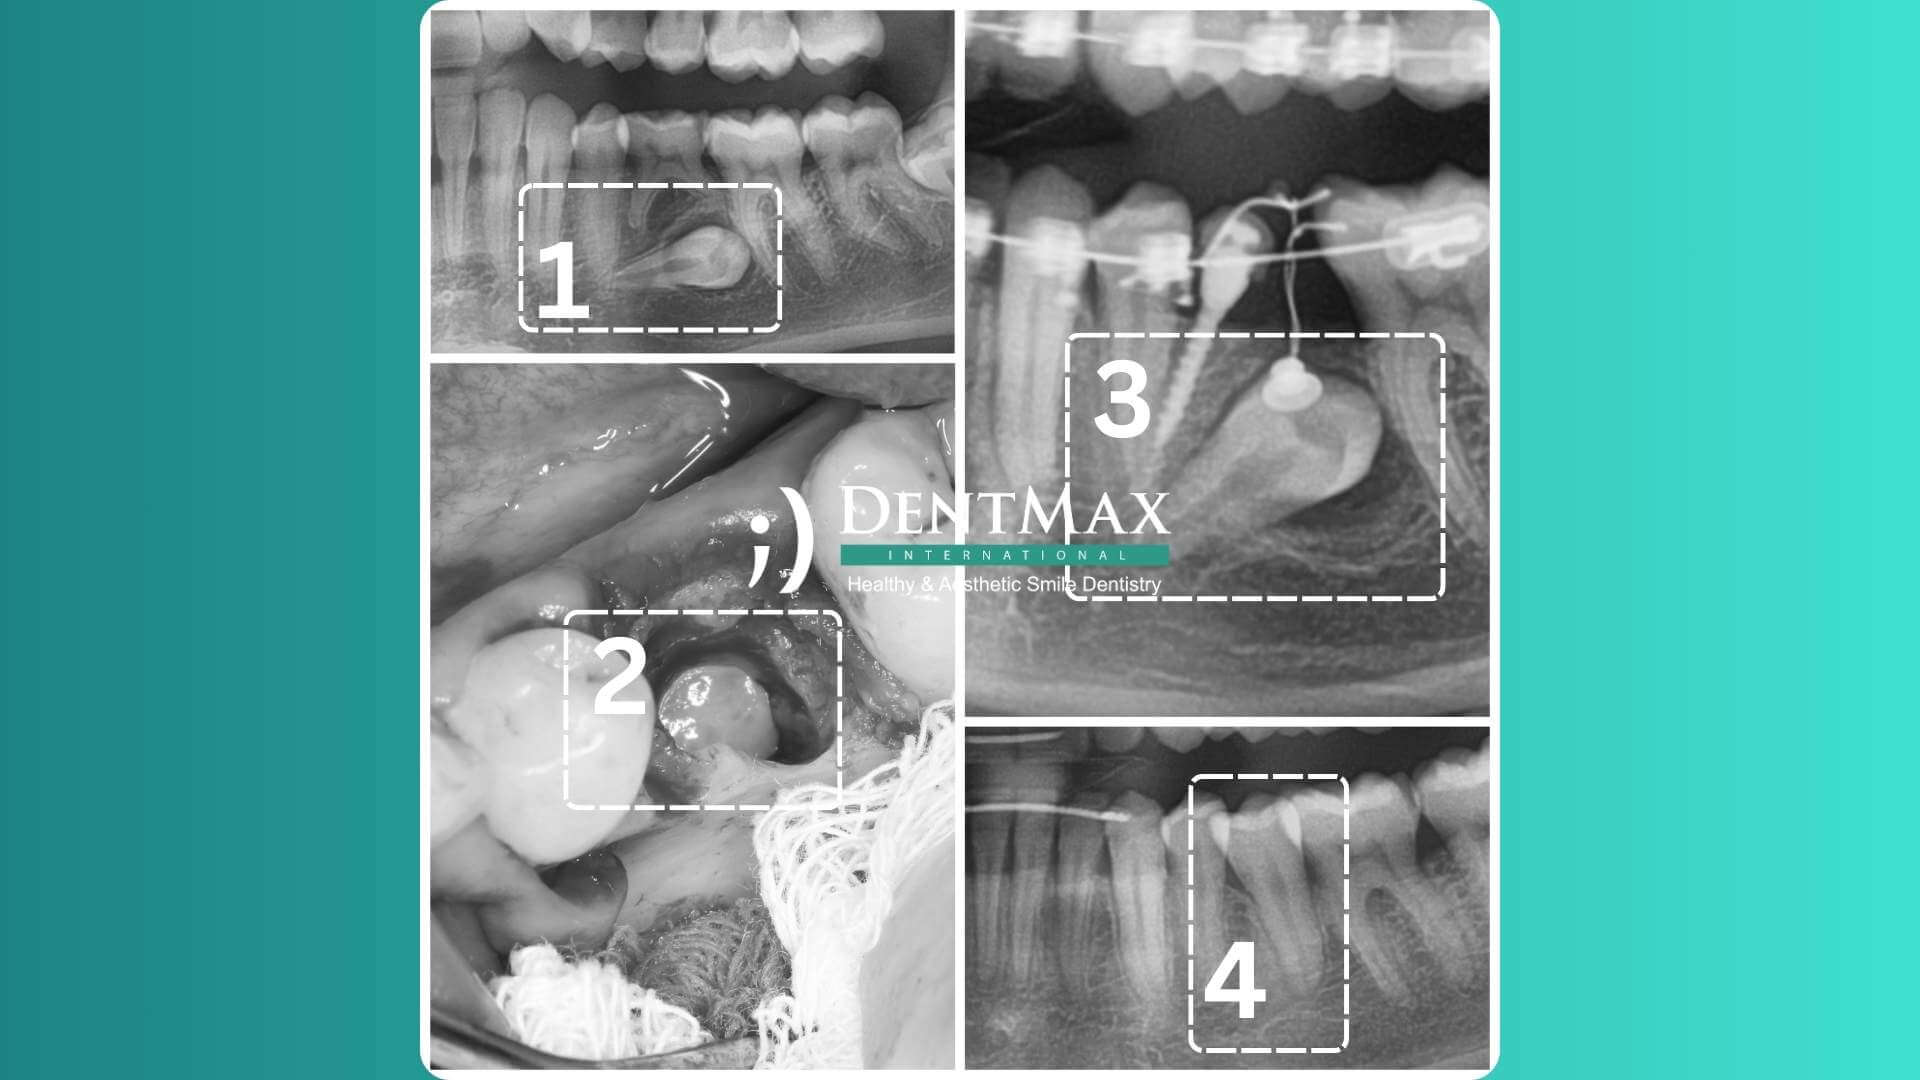

An orthodontist can detect impacted canine teeth using periapical x-rays, panoramic x-rays, or cone-beam computed tomography. Early diagnosis is crucial, and the first orthodontic examination is recommended between ages 6 and 7.

How is Impacted Tooth Treatment Performed?

Early diagnosis and intervention are the most desired approaches for impacted teeth. Without an orthodontic examination, early diagnosis is challenging. Misconceptions like "orthodontic treatments can only be done after ages 12-13" delay treatment. Modern orthodontics rejects this outdated belief, emphasizing the importance of early control. Orthodontic check-ups are recommended annually for primary school children. Treatment methods vary by age group:

• Early stage (ages 7-11): Orthodontic space creation and arch expansion.

• Later stage (ages 12+): Surgical exposure and orthodontic treatment to guide the tooth into the correct position.